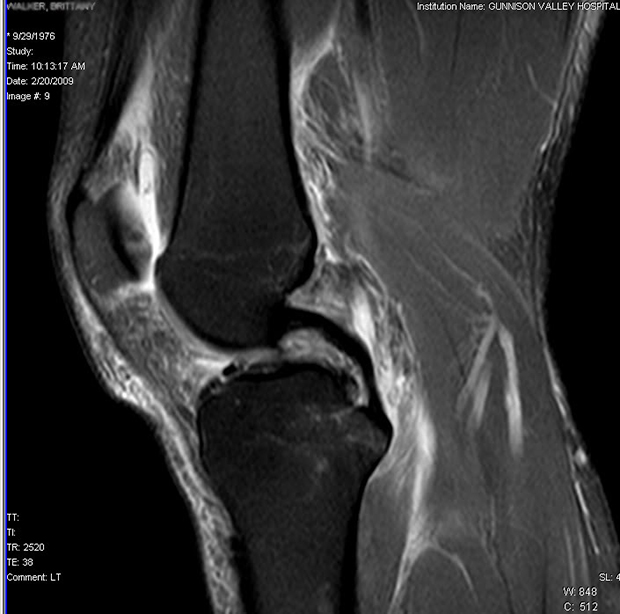

It’s the classic riding injury and one that no one wants to hear in the emergency room: ACL damage. God, even broken bones are a better prospect.

Surgery is the usual recovery route, and for many it can be a complete success, though as it changes the internal structure of the knee it can induce stresses and wear and tear in new areas, leading to new injuries and even arthritis in later life.